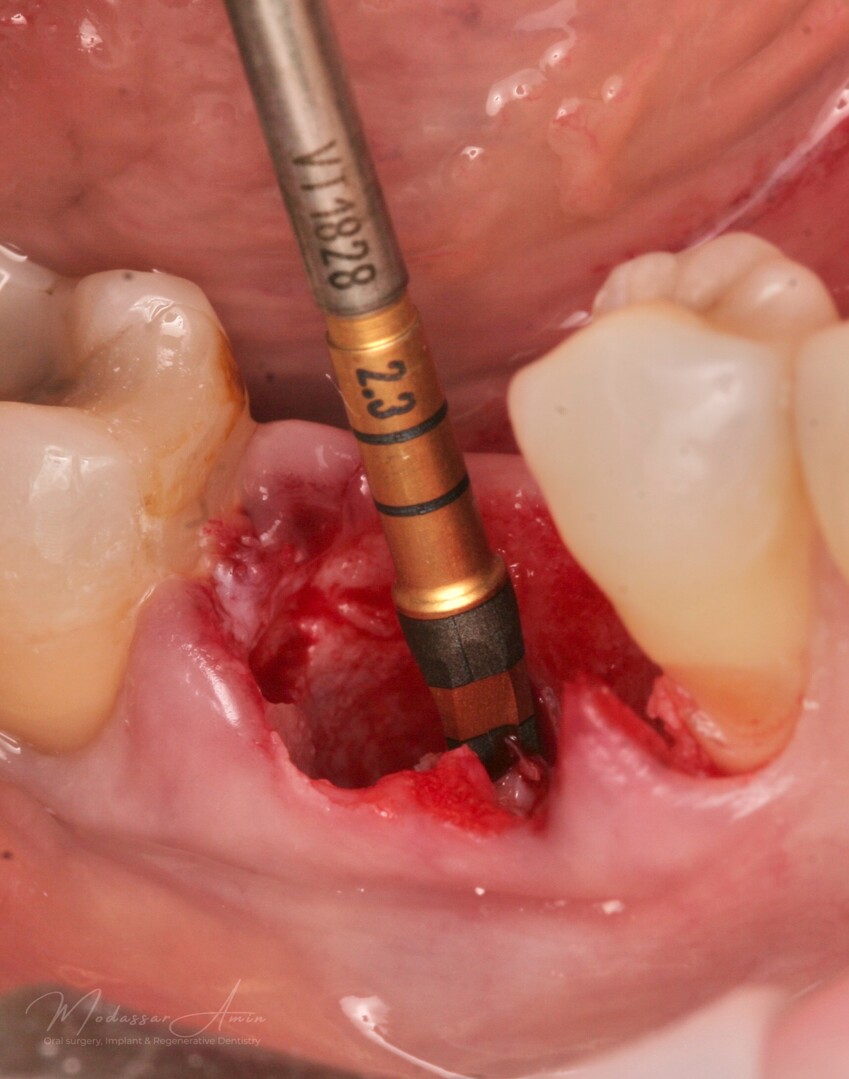

Versah bor 2.3

Septum ekspandert